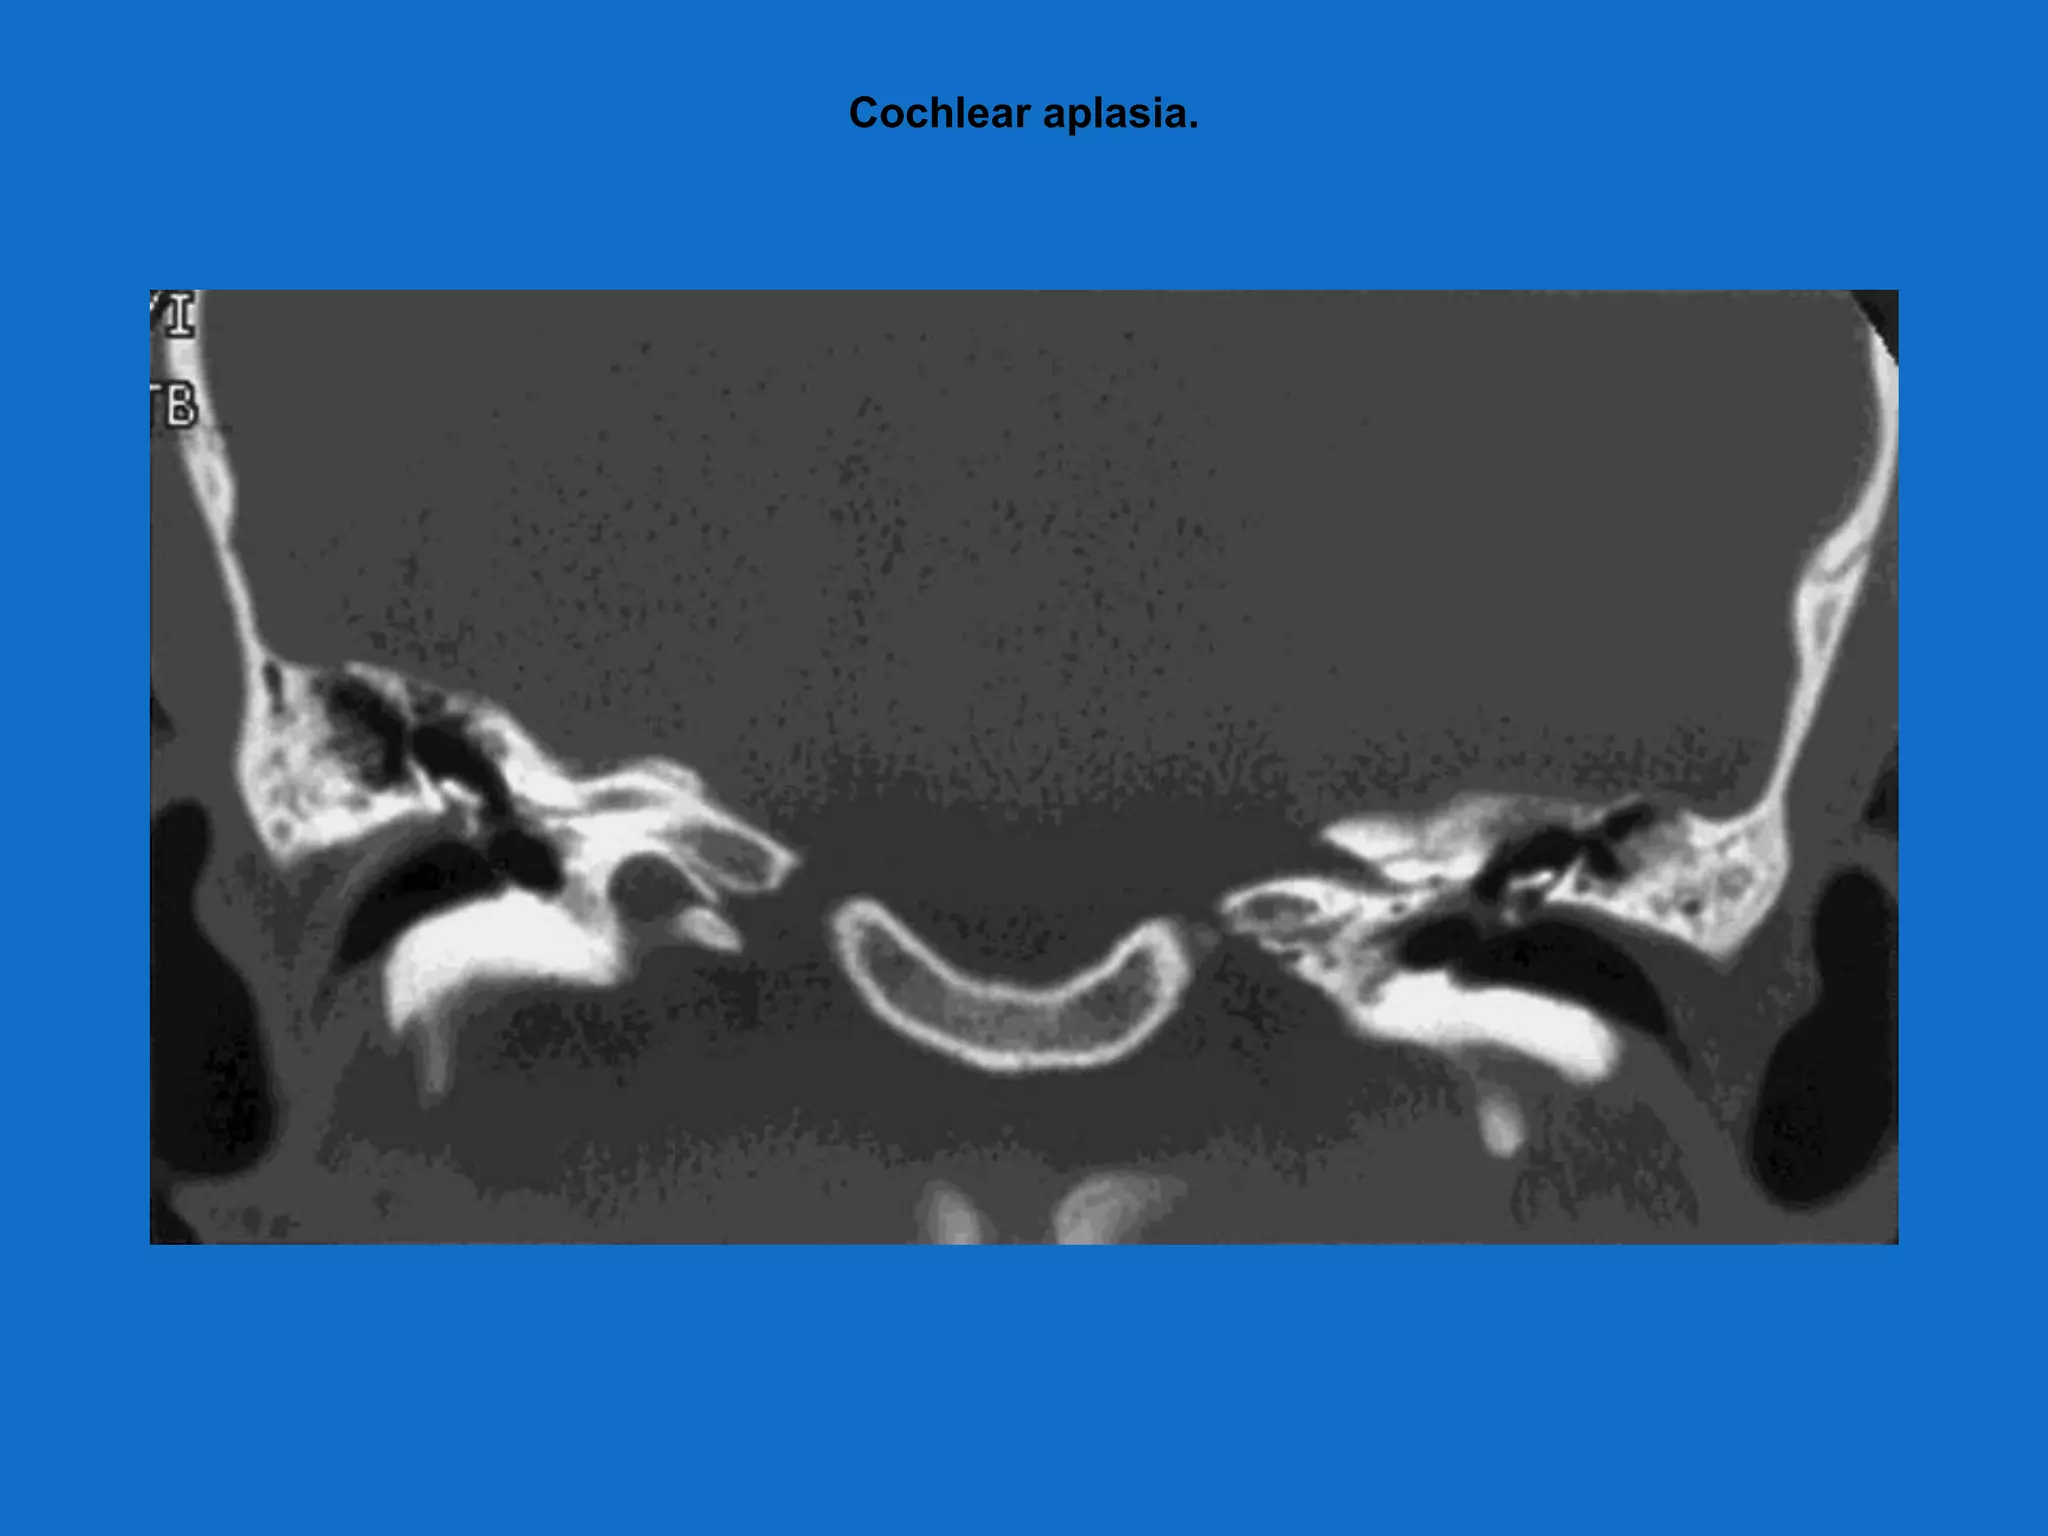

Radiology absolute requirements

• Presence of cochlea(either normal or

malformed)

• Presence of auditory nerve

• Combination of CT/MRI is performed

Cochlear aplasia.

Radiology absolute requirements •Presence of cochlea(either normal or malformed) • Presence of auditory nerve • Combination of CT/MRI is performed